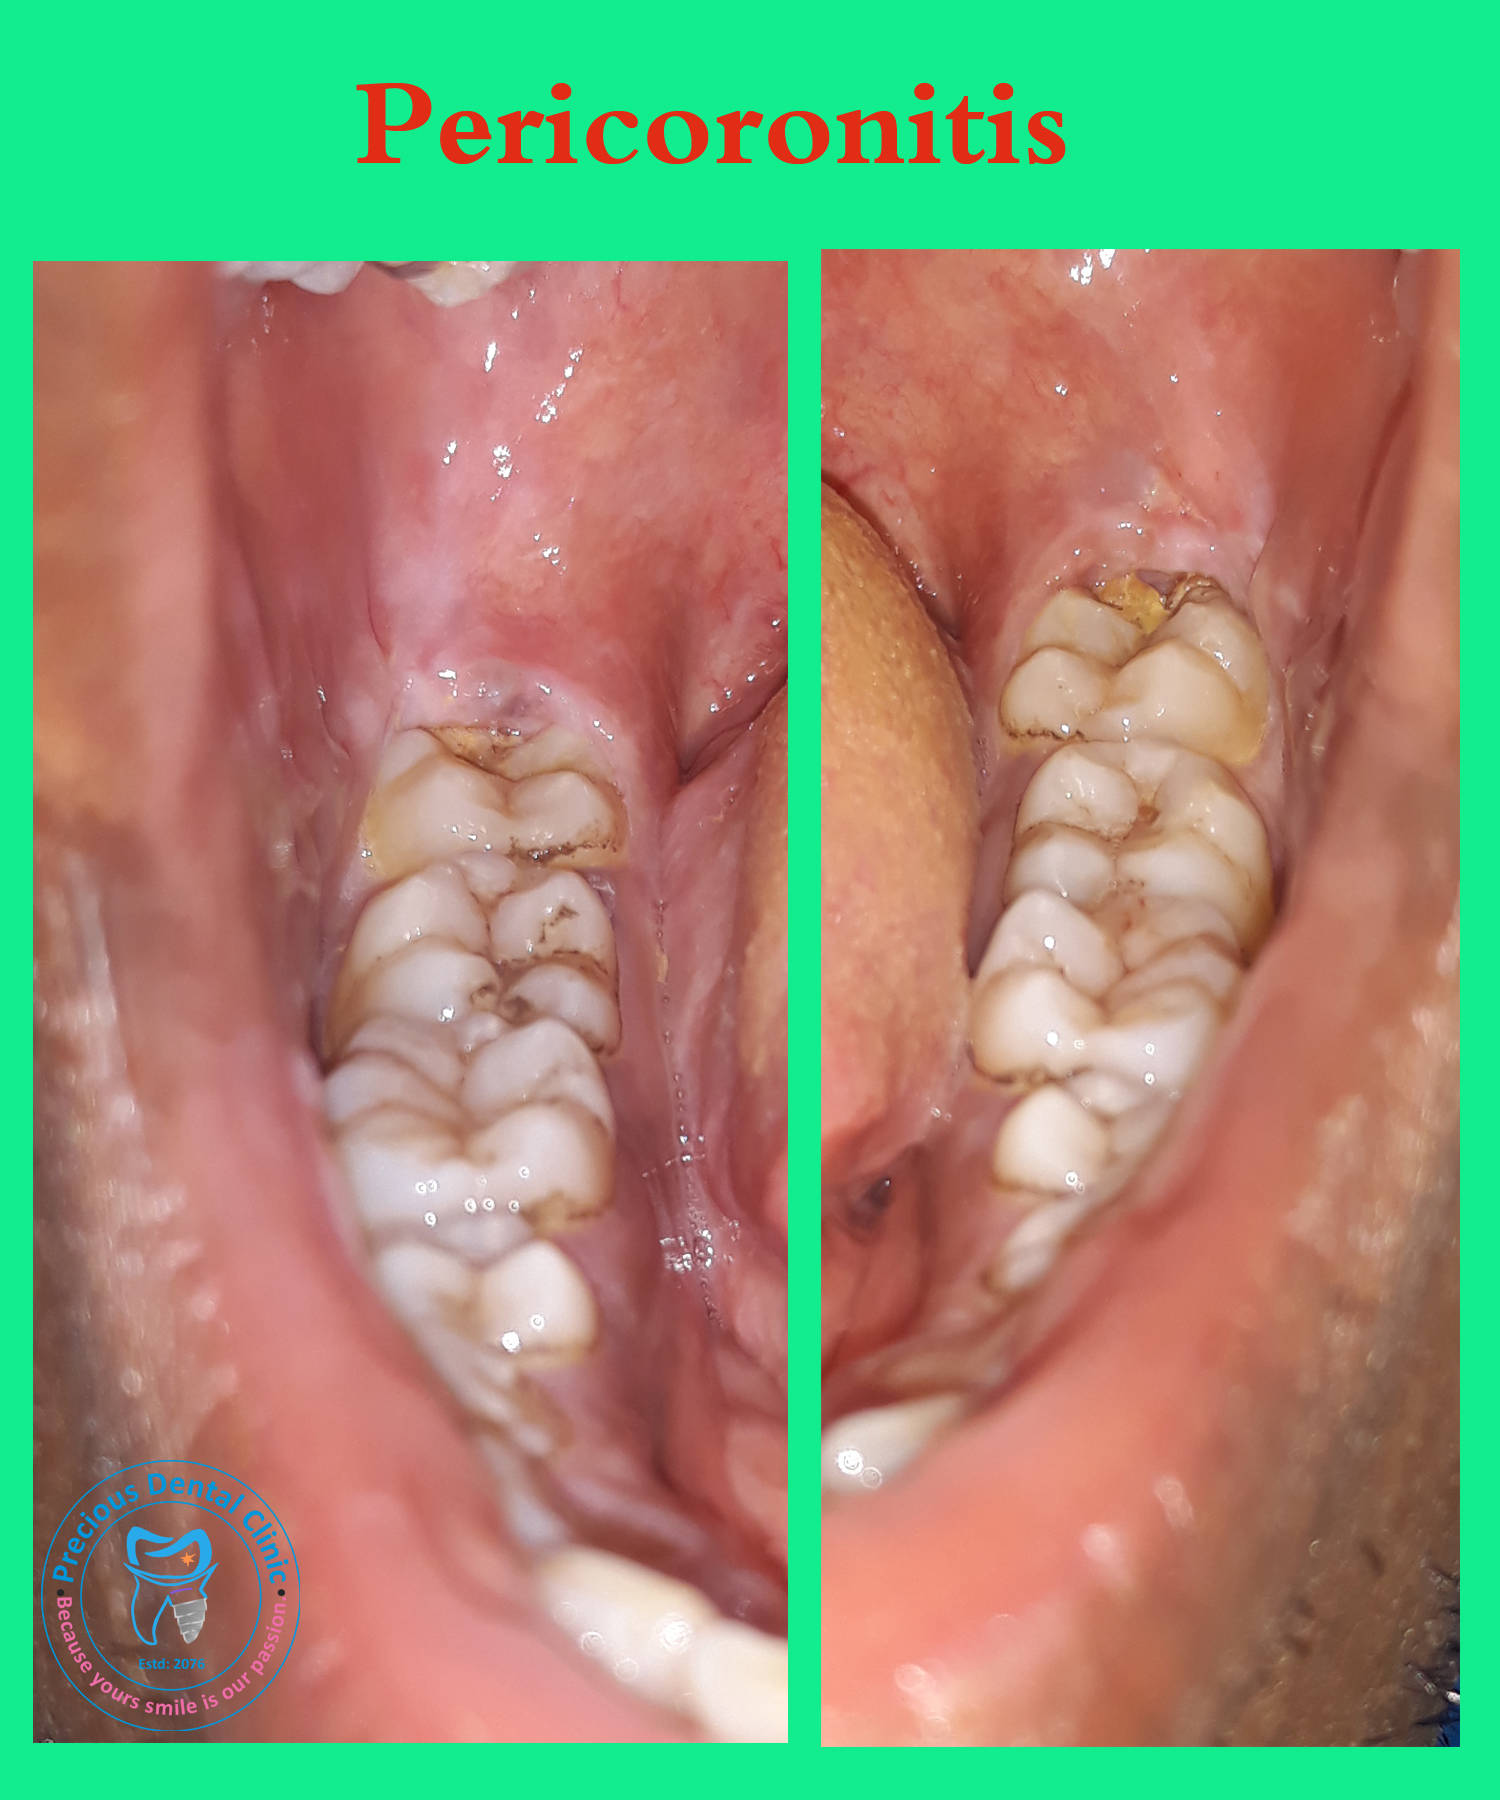

Collection of photos, here you will find the photos of doctor, services, environment and work.